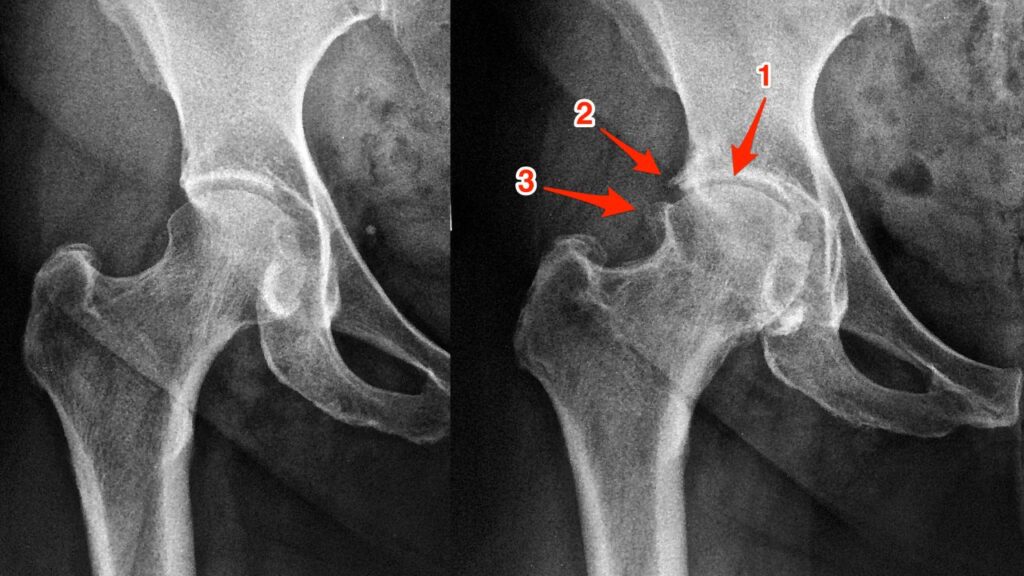

Exames e avaliação ortopédica especializada A investigação começa com um exame físico detalhado para identificar os pontos de dor e o grau de limitação funcional do paciente. Embora as radiografias ajudem a descartar fraturas ou deformidades ósseas evidentes, a ressonância magnética é o padrão-ouro para o diagnóstico, pois permite visualizar o estado da cartilagem em alta definição. Através dela, o ortopedista consegue classificar a gravidade da lesão e planejar a estratégia de tratamento mais adequada para cada caso.